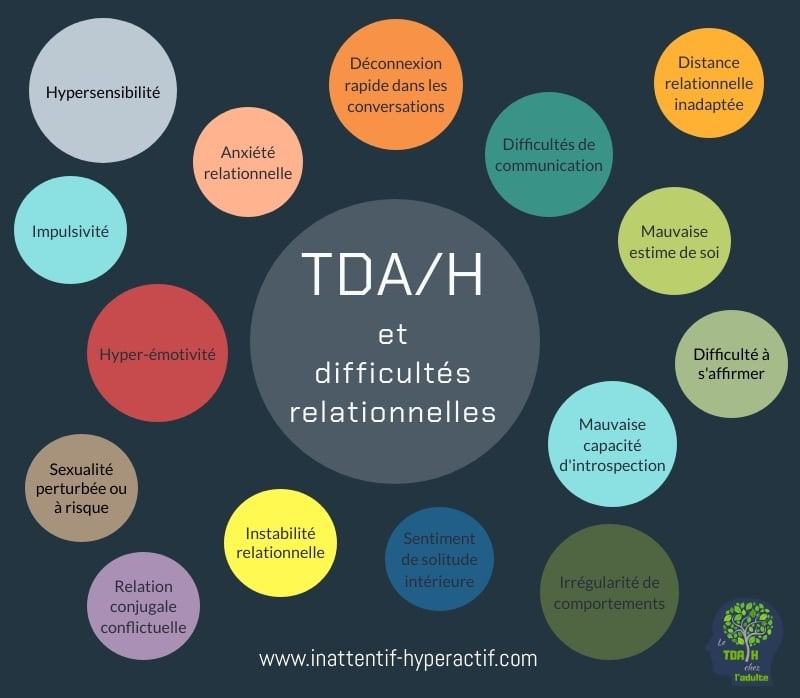

♠ 17 Difficultés relationnelles  Causes et conséquences des difficultés relationnelles avec le TDAH  Cliquez pour agrandir |

► Les

impulsifs sont en mode réactif et se fâchent facilement. – Leur tempérament bouillant peut provoquer des comportements intrusifs et dérangeants. – D’autres sont simplement provocateurs et beaucoup s’ennuient assez vite au contact des autres. – Cela commence très tôt durant l’enfance où les discussions des repas de famille les ennuient, et cela continue à l’âge adulte dans les réunions de travail. ► Certains ont du mal à s’exprimer car l’idée qui vient d’apparaitre est toujours prioritaire, même s’ils ont déjà commencé leur phrase sur un autre sujet. – Au-delà de deux ou trois personnes, beaucoup se sentent dissociés de la conversation en cours, ou en méta-position, tel un observateur de ce qui se dit, sans pouvoir entrer normalement dans la conversation. – D’autres développent une anxiété sociale ou simplement des paniques fréquentes avant leurs rendez-vous. ► Certains oublient leurs engagements, d’autres passent à côté des règles élémentaires de courtoisie ou de savoir-vivre. – Ils gaffent souvent en parlant trop impulsivement sans avoir suivi le début de la conversation. → Beaucoup d’irrégularité là aussi pour certains, avec des comportements différents dans le monde professionnel et familial, ou d’un contexte à l’autre, ou d’une journée à l’autre. – Comme ils passent d’un extrême à l’autre facilement, ils alternent souvent entre naïveté et méfiance selon les périodes et les évènements ►► Leur comportement à long terme dans un groupe est difficile, sauf s’ils ont un rôle spécial qui leur permet d’être attentif ou simplement d’exister (chef, orateur, formateur, consultant, expert, gai-luron, calimero, etc.). – Au travail, Ils ont du mal à suivre les règles et procédures établies pour faire à leur façon, à tort ou à raison. – Dans leur vie personnelle, ils peuvent être très différents, avec un sentiment de plus grande liberté, en pouvant choisir leurs amis et leurs activités, avec un besoin de variété et d’alternance.- ► Certains ont une personnalité évitante ou une phobie sociale plus ou moins prononcée. – D’autres passent leur temps à blâmer les autres, la société, les injustices qu’ils ressentent en permanence. – Ce sentiment d’injustice peut être réel, de par leur incapacité à élaborer des stratégies gagnantes avec leurs relations, mais il peut être exagéré du fait qu’ils n’adoptent pas les mêmes règles que la plupart des gens. – Beaucoup sont peu coopérants et veulent absolument faire les choses à leur manière, sans lire les instructions au complet s’il y en a. – On observe souvent chez eux des changements d’humeur imprévisibles. ► Ils sont souvent différents avec leurs proches avec lesquels leur hypersensibilité émotionnelle domine. – On constate plus de problèmes familiaux et de problèmes de couples chez les adultes TDAH, avec plus de divorces. – Leur sentiment de retrouver la liberté peut atténuer l’échec s’ils sont relativement jeunes. – Il y a chez les adolescents plus de relations sexuelles précoces et non protégées, avec beaucoup de grossesses non désirées et de maladies sexuellement transmissibles. – Certains n’ont pas assez d’attention pour mener à bien leur relation sexuelle et se déconcentrent durant l’acte. ► Ils ont souvent une mauvaise capacité d’introspection sur eux-mêmes et leurs comportements en société. – Les moins confiants vont exagérer leurs défauts, leurs petits dysfonctionnements ou leurs difficultés relationnelles. – Les plus confiants vont au contraire minimiser leurs problèmes de comportements en ne mesurant pas l’impact qu’ils ont sur les autres jusqu’à les blesser. – Parmi eux, plusieurs sont en opposition permanente qui va jusqu’à des troubles de conduite en société. |

| ► La